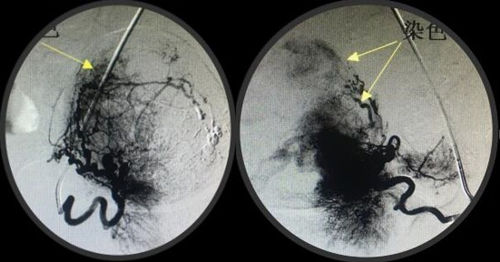

经人介绍来到乐鱼手机站入口介入科,经李建国主任术前评估,患者无介入手术禁忌症,于4月16日早9点行介入手术。术中采用右肱动脉穿刺、超选择双侧子宫动脉造影栓塞术,手术顺利历时约40分钟,成功保全了子宫。术后患者步入病房,避免了因卧床制动而形成下肢深静脉血栓的风险...